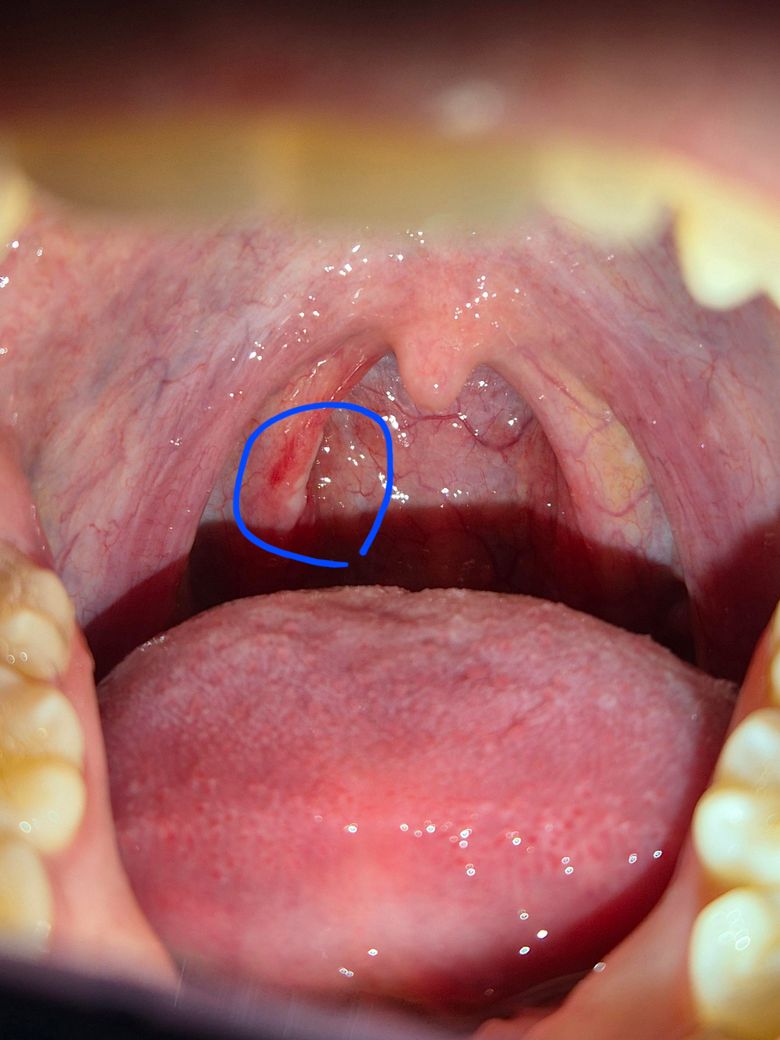

사진상 편도쪽인거같긴한데 삼킬때마다 통증이 있었거든요.. 5월 7일경부터 생긴거같은데 사진상 동그라미 해둔 저 하얀게 뭔지 궁금합니다.. 염증인건가요?

해당 부위는 편도와 연구개(입천장 뒤쪽) 경계 쪽이며, 그 하얀 점은 편도결석(편도석) 또는 표재성 농(고름)일 가능성이 높습니다. 편도염 초기에는 이처럼 하얀 찌꺼기처럼 보이는 삼출물(염증 분비물)이 생길 수 있고, 삼킬 때 통증이 있는 것도 급성 편도염이나 인두염에서 흔히 나타나는 증상입니다.

편도결석은 보통 냄새나는 덩어리로, 음식 찌꺼기와 박테리아가 뭉쳐 생기며 큰 문제가 되진 않지만 반복적으로 생기면 통증과 불편감을 유발할 수 있어요

하지만 지금처럼 삼킴 통증이 며칠째 지속되고 있다면, 바이러스성 혹은 세균성 편도염일 수 있으므로 항생제 치료가 필요한 경우로 보여요. 지금 이비인후과 진료를 권하고 고열, 전신 쇠약감, 통증이 심해지는 경우엔 꼭 이비인후과 진료를 보시길 권합니다.